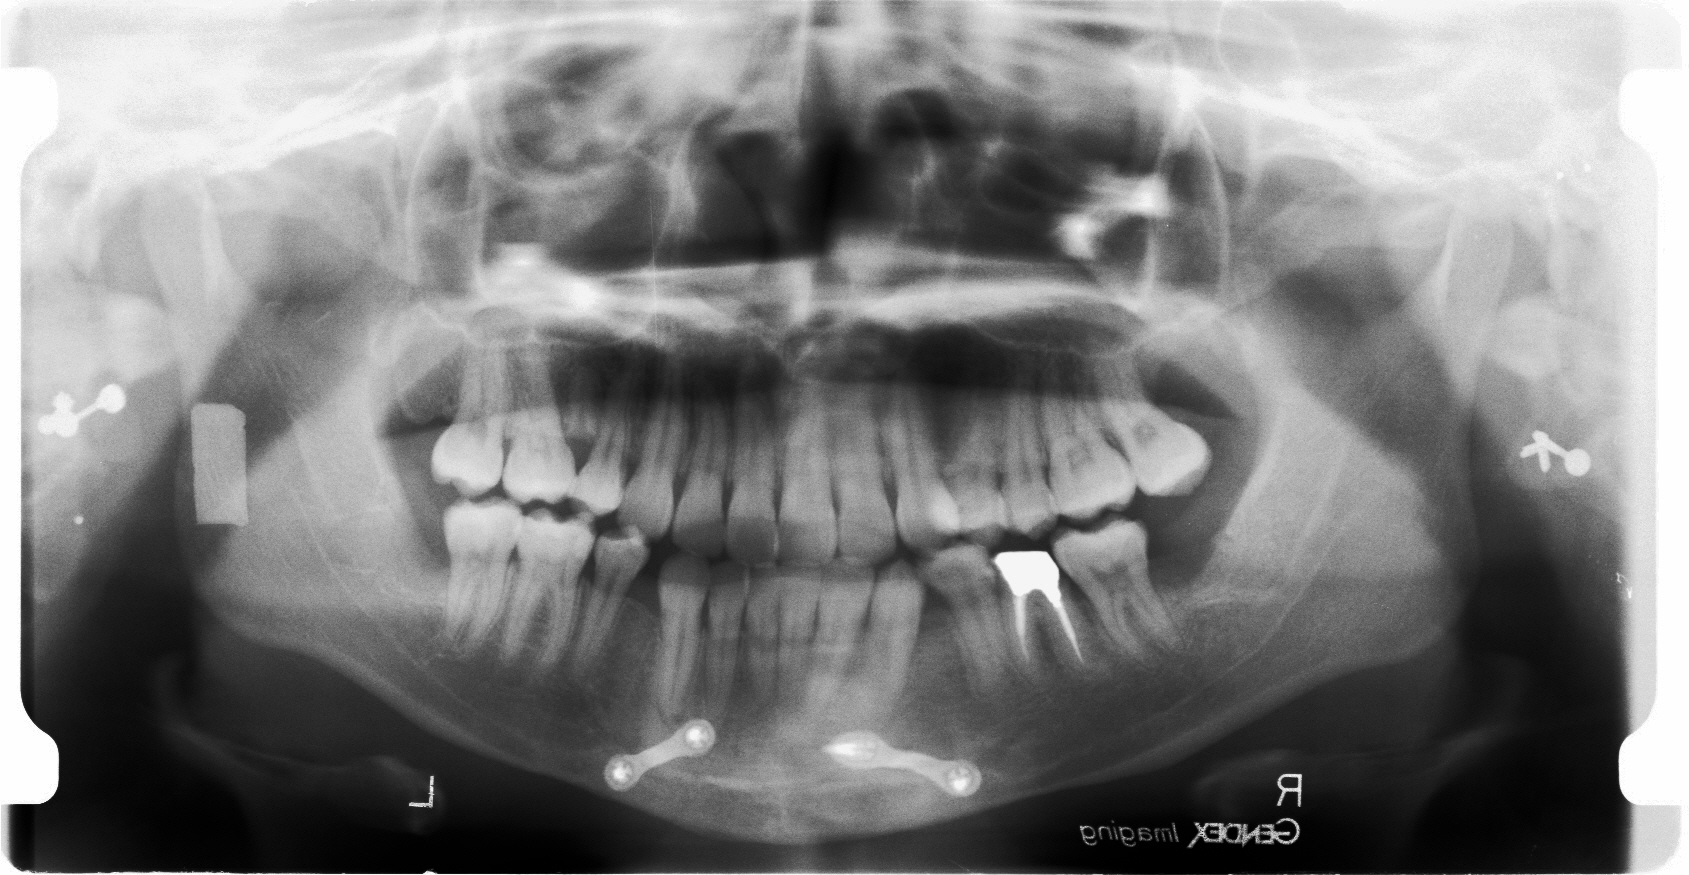

下顎には外科処置後での犬歯の後ろに少しのスペースが残っています。 もともと過度な受け口であった為下顎骨を少し削って短くしました。

下顎を切断してメタルでつないであるのが見受けられます。

今回のケースは下顎がしゃくれている為外科的に短く切除を行った後の術後矯正です。